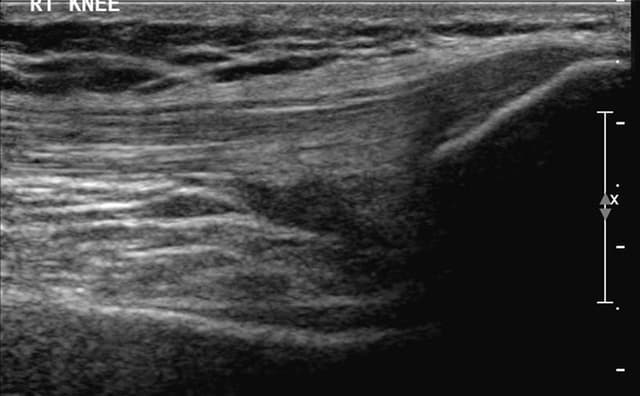

Enables clear visualization of anatomical landmarks, needle movements, and injection sites.

Hands-on Interventional Training – Introducing simulator-based hands-on interventional training. These are one-of-a-kind and replicate human anatomy, allowing users to perform injections under ultrasound guidance like performing real-world procedures.